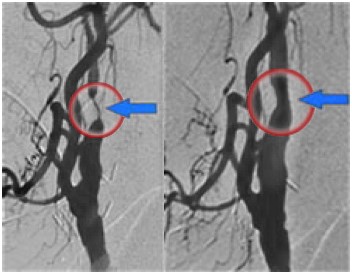

Après avoir bien visualisé le rétrécissement de l’artère carotide par injection de produit de contraste, le médecin dilate la sténose à l’aide d’un ballon d’angioplastie puis implante un stent (ou endoprothèse) pour redonner un calibre normal de l’artère. Différents dispositifs peuvent être utilisés afin de limiter le risque de migration de caillot ou de fragment de plaque d’athérome dans les artères du cerveau.